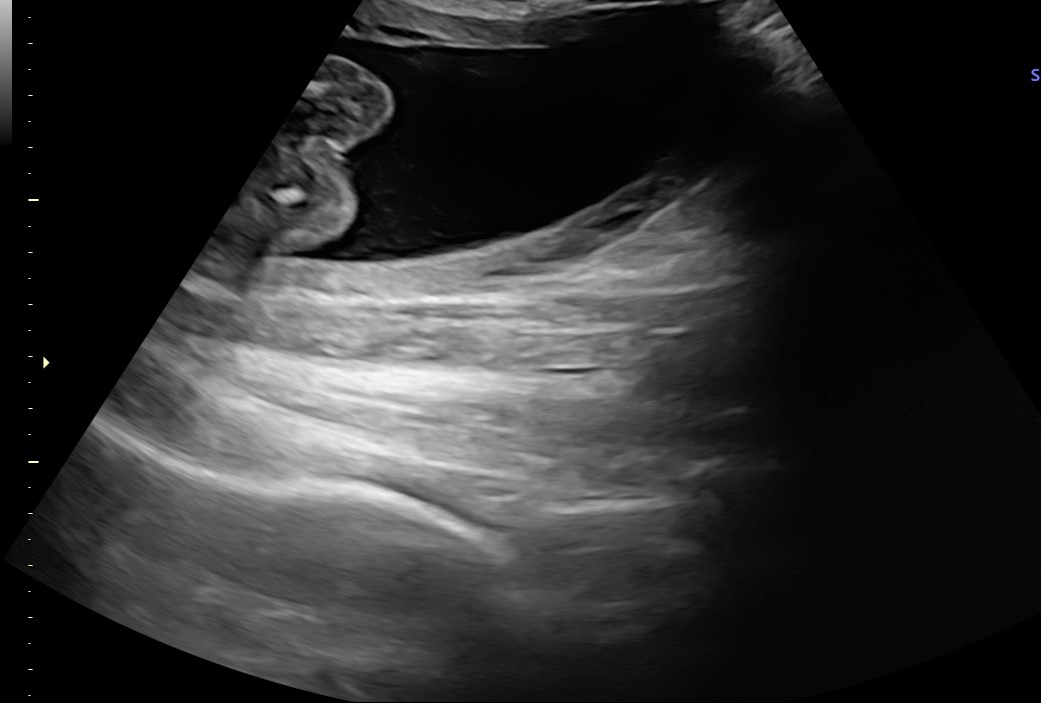

Aké pohlavie dieťatka vidíte na fotke z ultrazvuku?

bola som na sone a zaujíma ma pohlavie.

mrzí ma to, ale popisované UZV patrí do kompetencie lekára.